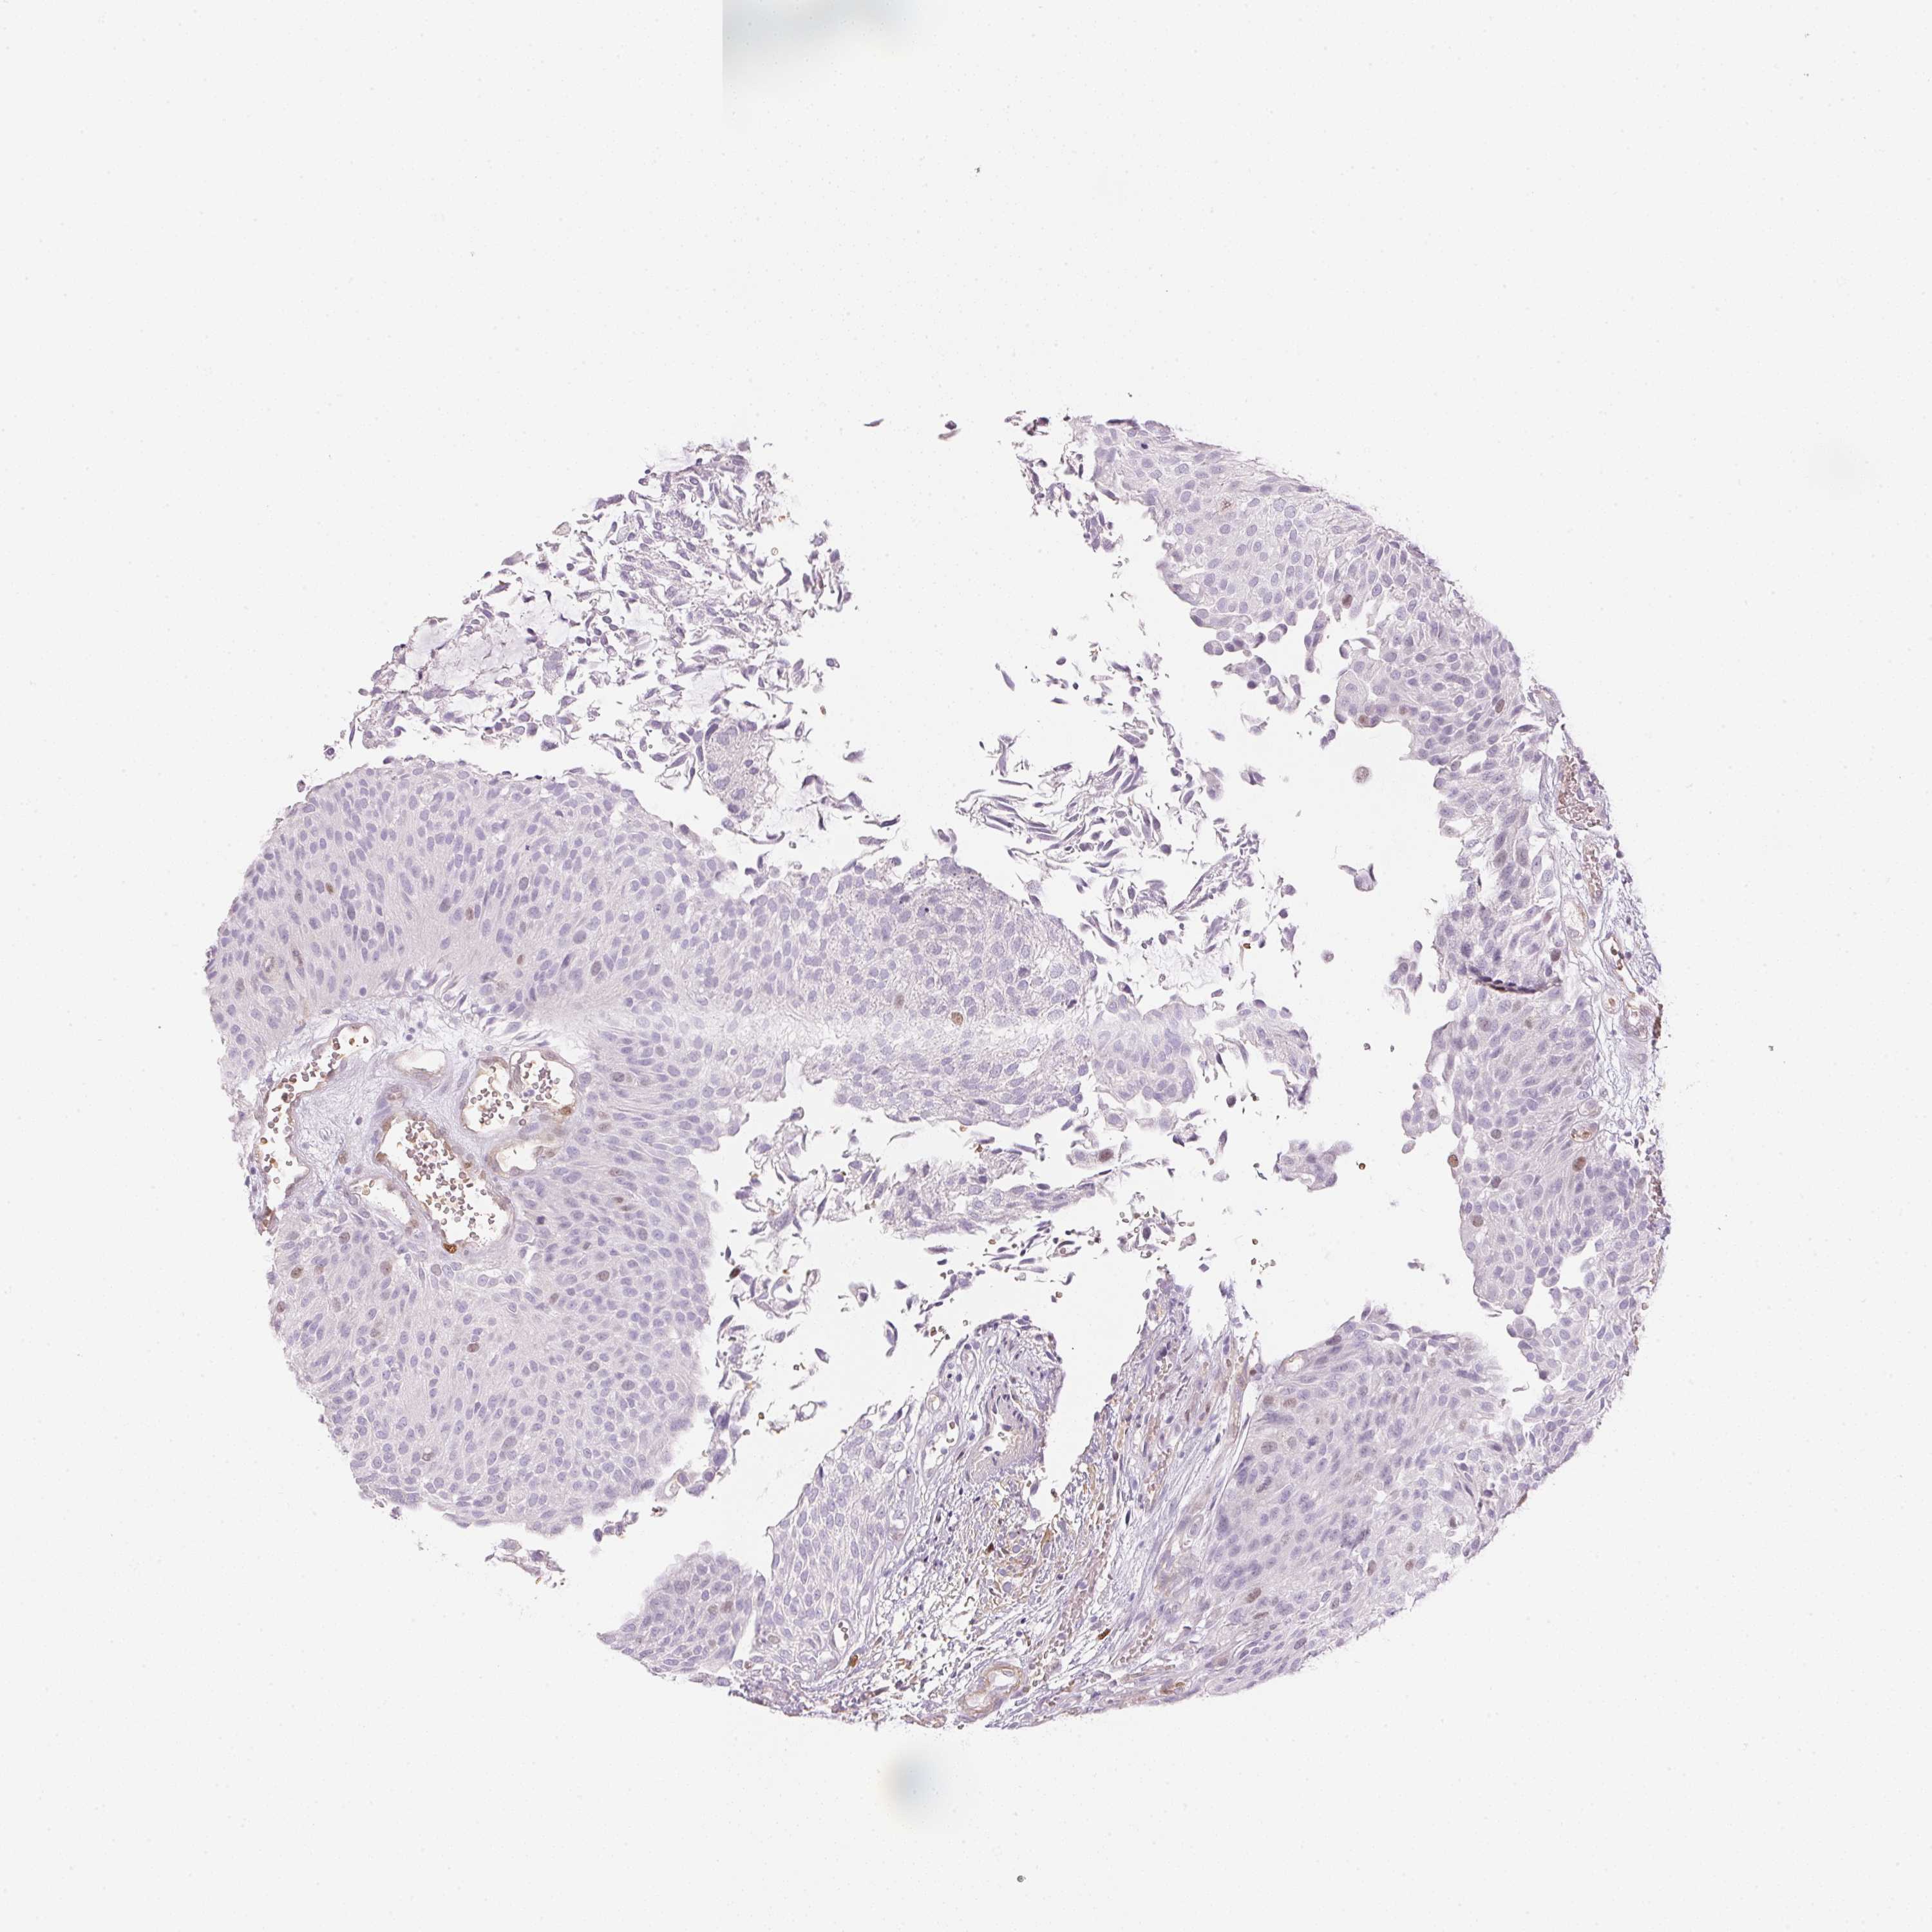

UROTHELIAL CANCER - Protein expressioni

A mouse-over function shows sample information and annotation data. Click on an image to view it in a full screen mode. Samples can be filtered based on level of antibody staining by selecting one or several of the following categories: high, medium, low and not detected. The assay and annotation is described here.

Note that samples used for immunohistochemistry by the Human Protein Atlas do not correspond to samples in the TCGA dataset.

Antibody stainingi

Antibody staining in the annotated cell types in the current human tissue is reported as not detected, low, medium, or high, based on conventional immunohistochemistry profiling in selected tissues. This score is based on the combination of the staining intensity and fraction of stained cells.

Each image is clickable and will lead to virtual microscopy that enables deeper exploration of all samples and also displays staining intensity scores, fraction scores and subcellular localization as well as patient and tissue information for each sample.

Antibody HPA051778

Antibody HPA058590

Antibody CAB001721

Urothelial carcinoma, High grade

Urothelial carcinoma, Low grade

Urothelial carcinoma, NOS